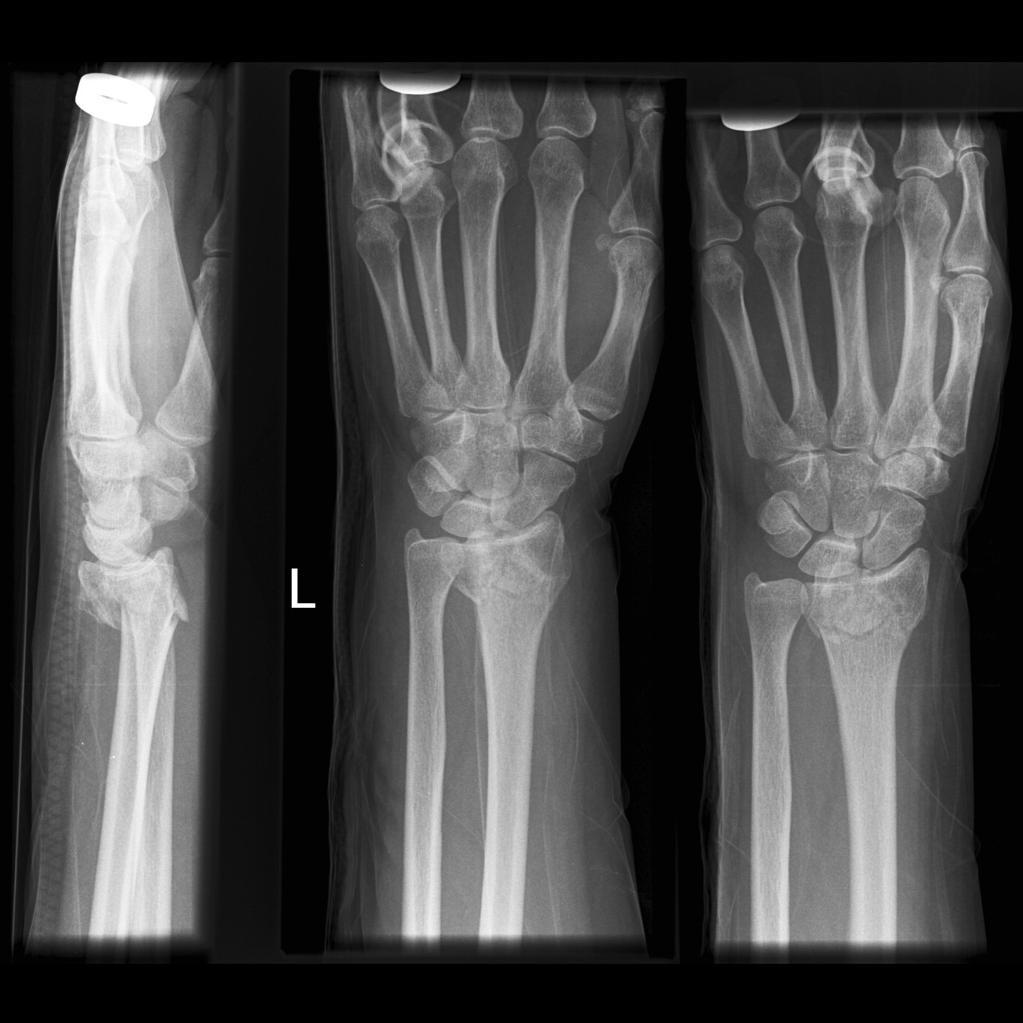

What is a Colles’ fracture?

An extra articular fracture of the distal radius within an inch of the articular surface and with dorsal displacement or angulation

A Colles’ fracture is commonly associated with fracture of what else?

Ulnar styloid process

What is a Smith’s fracture?

A volarly displaced or angulated extra-articular fracture of the distal radius

A _________ fracture involves a volarly displaced distal radius, whereas a _________ involves a dorsally displaced distal radius

A Smith’s fracture involves a volarly displaced distal radius, whereas a Colles’ involves a dorsally displaced distal radius

What is a Barton’s fracture?

Intra-articular fractures of the distal radius involving dorsal or volar rims

Carpal bones of the wrist sublux with the displaced rim fragment